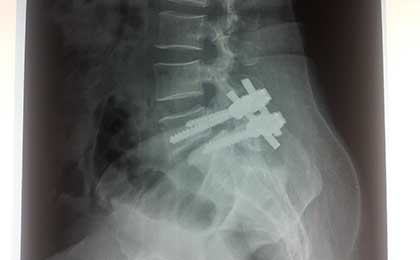

post op L5 S1 FIXATION

Spine Fixation Lumbar Spine

• Spine Fixation Lumbar Spine

post op dorsolumbar fixation x ray